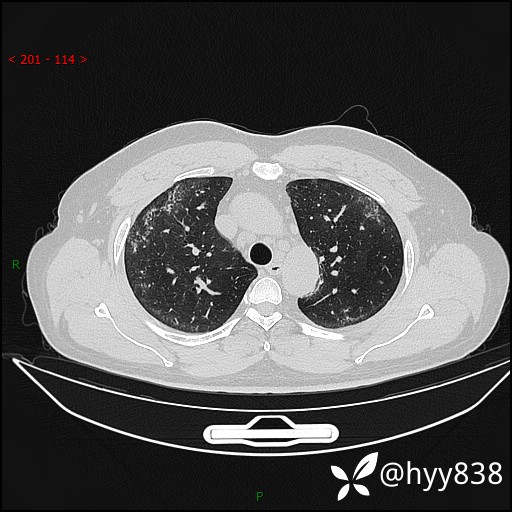

第一次胸部CT

第二次CT(7天后)